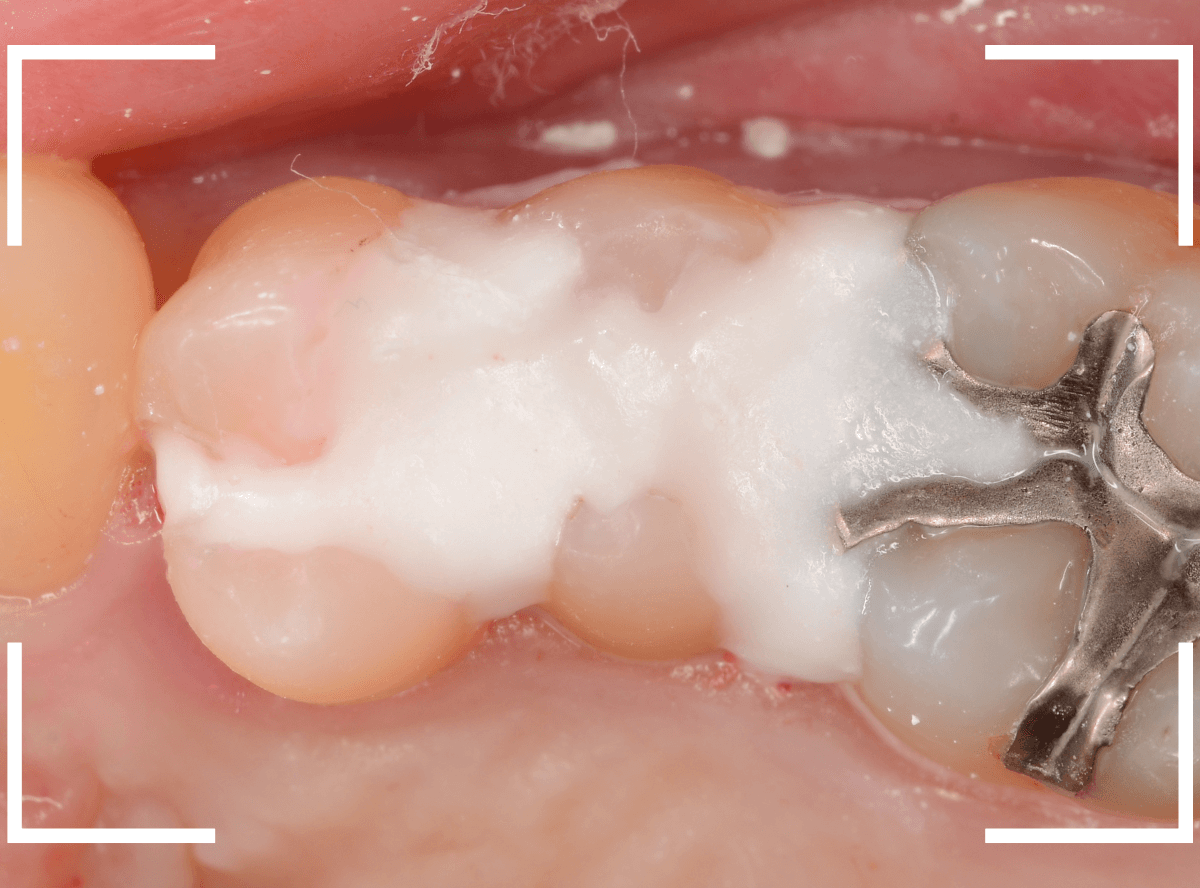

Case.21 神経に達しそうな2本の大きな虫歯

上の小臼歯の側面が明らかに虫歯になっている患者さんです。

患者さんは特に症状を感じてなさそうですが、恐らくは中で大きな虫歯になっているでしょう。

このように、自覚症状からだけでは虫歯の状況は診できません。

レントゲン写真で確認します。

青い線が歯の神経、赤い線が虫歯と思われる部分です。

2本とも、神経に達してしまいそうな大きな虫歯であると思われます。

まず、奥の歯のつめものを外してから、虫歯の治療を開始します。

手前の歯が大きな虫歯が見えてきました。

神経に達してしまいそうな虫歯ですので、ある程度削ったところで、少しずつエキスカという道具で掻き出すようにして、虫歯を除去します。

虫歯は歯を溶かして進行しますので、骨よりも固い歯もちょっと掻き出すとボロボロと崩れるようになってしまっています。

かなり虫歯を除去したところで、手前の歯は神経が顔を出してしまいました(露髄といいます)。

神経を除去する治療が必要かもしれないです。

全ての虫歯を除去したところです。

幸い、後ろの歯は薄皮一枚のところで神経まで達していない虫歯ですんでいましたが、大きな虫歯だった事には変わりありません。

いつものように、神経が痛み出さないように祈りつつ、お薬で保護して経過観察します。

虫歯は症状からだけでは判断できませんが、定期受診によって、このような大きな虫歯の処置は避けられる事がほとんどです。

かならず歯科の定期受診をしてくださいね。